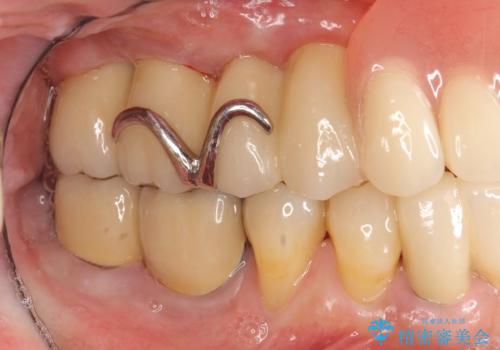

- 歯が全体的にグラグラし、しっかりと物が噛めなくなり歯周病治療を希望され来院されました。

残すことのできる歯、残すことのできない歯を初期治療を進めながら見極め、最終的に臼歯部はインプラント、上顎前歯は入れ歯による補綴計画となりました。